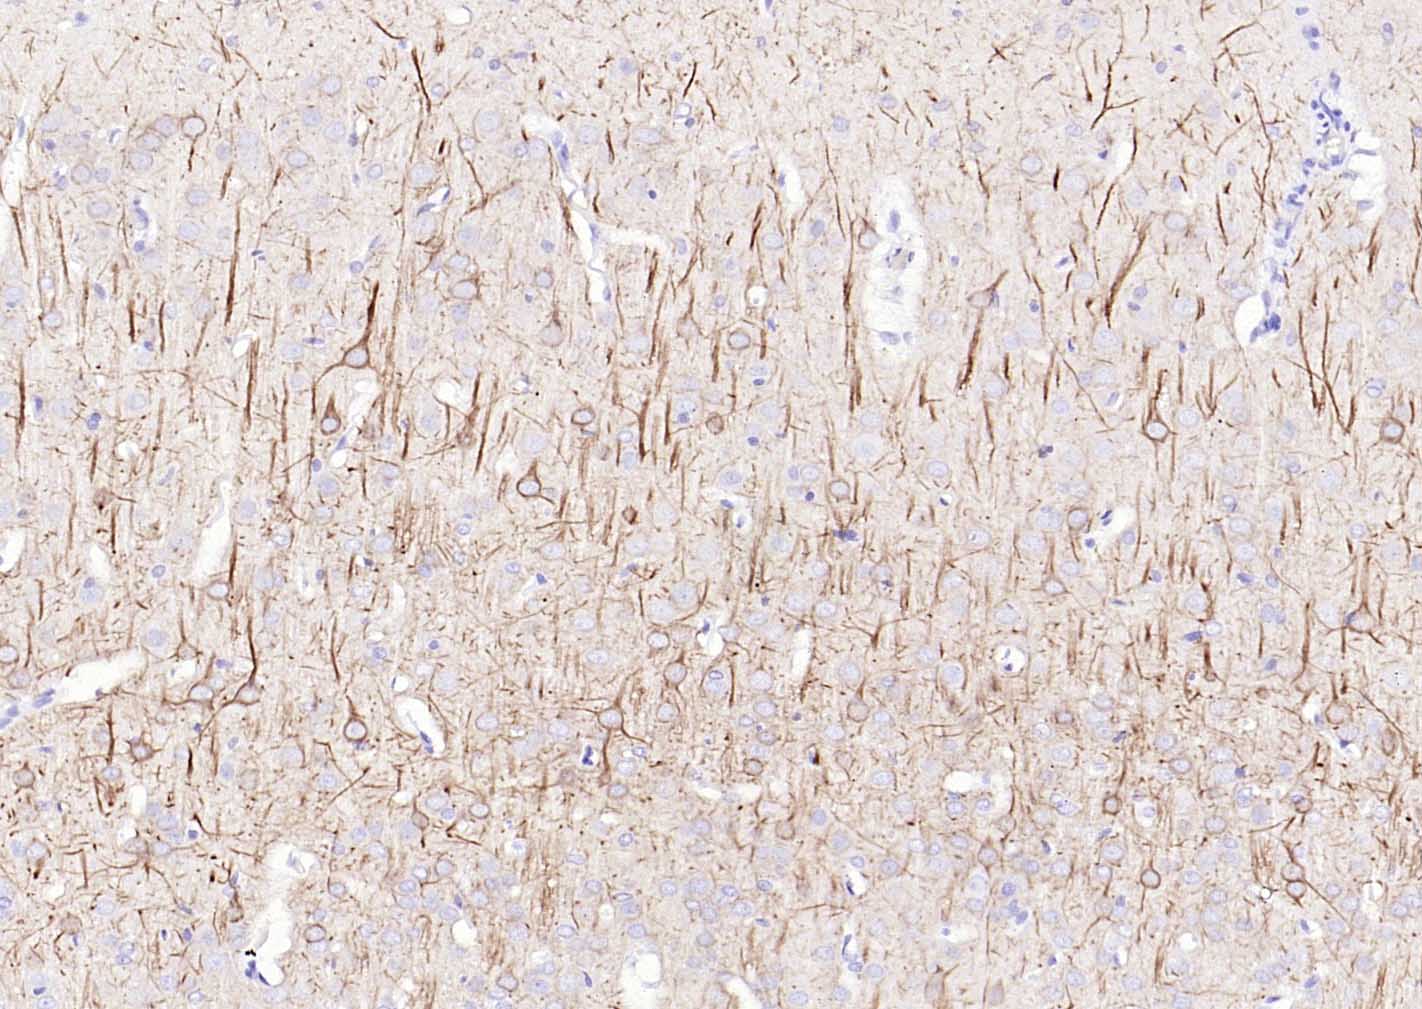

Paraformaldehyde-fixed, paraffin embedded (rat Cerebrum); Antigen retrieval by boiling in sodium citrate buffer (pH6.0) for 15min; Block endogenous peroxidase by 3% hydrogen peroxide for 20 minutes; Blocking buffer (normal goat serum) at 37°C for 30min; Antibody incubation with (NF-L) Polyclonal Antibody, Unconjugated (bs-0707R) at 1:100 overnight at 4°C, followed by operating according to SP Kit(Rabbit) (sp-0023) instructionsand DAB staining.

Paraformaldehyde-fixed, paraffin embedded (human cerebellum); Antigen retrieval by boiling in sodium citrate buffer (pH6.0) for 15min; Block endogenous peroxidase by 3% hydrogen peroxide for 20 minutes; Blocking buffer (normal goat serum) at 37°C for 30min; Antibody incubation with (NF-L) Polyclonal Antibody, Unconjugated (bs-0707R) at 1:100 overnight at 4°C, followed by operating according to SP Kit(Rabbit) (sp-0023) instructionsand DAB staining.

Paraformaldehyde-fixed, paraffin embedded (rat cerebellum); Antigen retrieval by boiling in sodium citrate buffer (pH6.0) for 15min; Block endogenous peroxidase by 3% hydrogen peroxide for 20 minutes; Blocking buffer (normal goat serum) at 37°C for 30min; Antibody incubation with (NF-L) Polyclonal Antibody, Unconjugated (bs-0707R) at 1:100 overnight at 4°C, followed by operating according to SP Kit(Rabbit) (sp-0023) instructionsand DAB staining.

Paraformaldehyde-fixed, paraffin embedded (mouse cerebellum); Antigen retrieval by boiling in sodium citrate buffer (pH6.0) for 15min; Block endogenous peroxidase by 3% hydrogen peroxide for 20 minutes; Blocking buffer (normal goat serum) at 37°C for 30min; Antibody incubation with (NF-L) Polyclonal Antibody, Unconjugated (bs-0707R) at 1:100 overnight at 4°C, followed by operating according to SP Kit(Rabbit) (sp-0023) instructionsand DAB staining.

Paraformaldehyde-fixed, paraffin embedded (rat spinal cord); Antigen retrieval by boiling in sodium citrate buffer (pH6.0) for 15min; Block endogenous peroxidase by 3% hydrogen peroxide for 20 minutes; Blocking buffer (normal goat serum) at 37°C for 30min; Antibody incubation with (NF-L) Polyclonal Antibody, Unconjugated (bs-0707R) at 1:100 overnight at 4°C, followed by operating according to SP Kit(Rabbit) (sp-0023) instructionsand DAB staining.

Paraformaldehyde-fixed, paraffin embedded (mouse spinal cord); Antigen retrieval by boiling in sodium citrate buffer (pH6.0) for 15min; Block endogenous peroxidase by 3% hydrogen peroxide for 20 minutes; Blocking buffer (normal goat serum) at 37°C for 30min; Antibody incubation with (NF-L) Polyclonal Antibody, Unconjugated (bs-0707R) at 1:100 overnight at 4°C, followed by operating according to SP Kit(Rabbit) (sp-0023) instructionsand DAB staining.